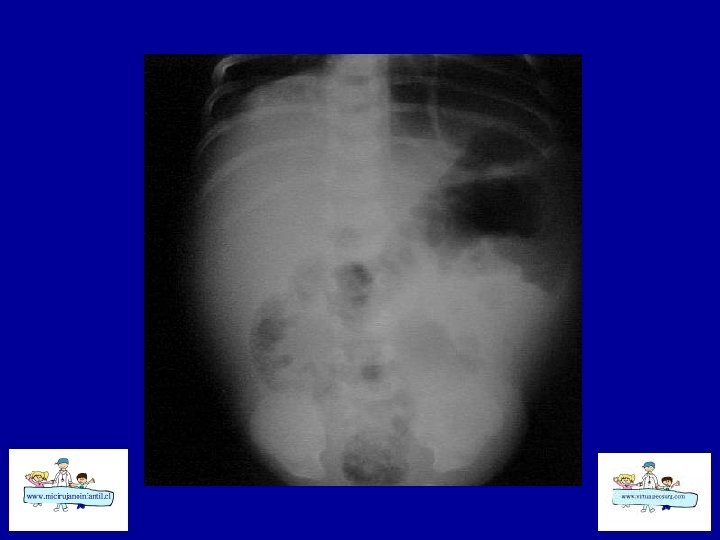

ECN-RADIOLOGÍA SIMPLE • • Distensión de asas Pneumatosis intestinal Asa fija (centinela) Gas Porta Edema de pared Ascitis Aire libre

ECN- CLASIFICACION (Bell) Etapa I: sospecha a CEG, sepsis inicial, Rx. distensión de asas moderada Etapa II: confirmada Ileo, sepsis más intensa , Rx: Ileo – pneumatosis b Hematoquezia Celulitis de pared, masa, grave, Rx: ascitis, gas porta Etapa III: grave Muy grave, CID, peritonitis Rx: ascitis Rx : pneumope ritoneo